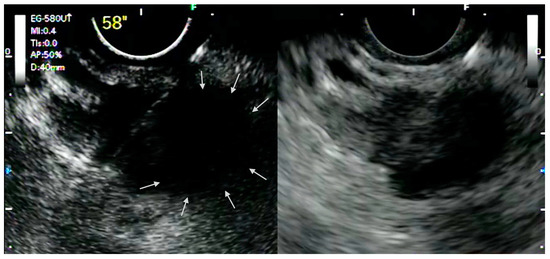

- Minaga, K.; Takenaka, M.; Omoto, S.; Miyata, T.; Kamata, K.; Yamao, K.; Imai, H.; Watanabe, T.; Kitano, M.; Kudo, M. A case of successful transluminal drainage of walled-off necrosis under contrast-enhanced harmonic endoscopic ultrasonography guidance. J. Med Ultrason. 2018, 45, 161–165. [Google Scholar] [CrossRef]

- Badea, R.; Seicean, A.; Procopet, B.; Dina, L.; Osian, G. Pseudoaneurysm of Splenic Artery Ruptured in Pancreatic Pseudocyst and Complicated by Wirsungorrhagia: The Role of the Ultrasound Techniques and Contrast Substances. Ultraschall Med. Eur. J. Ultrasound 2010, 32, 205–207. [Google Scholar] [CrossRef] [PubMed]